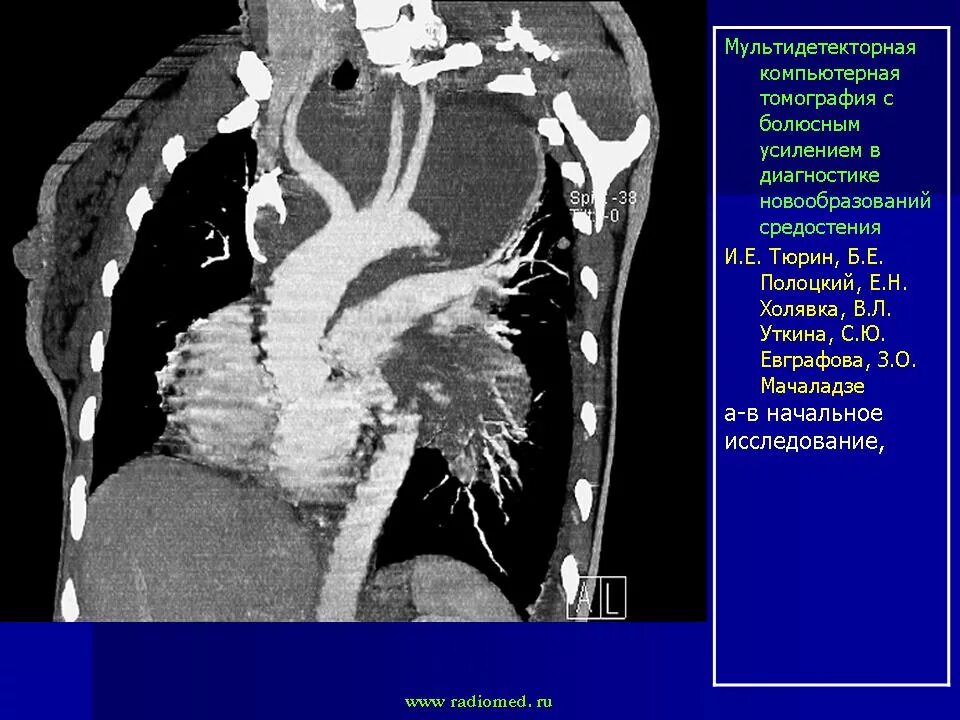

Метастазы в средостении легких